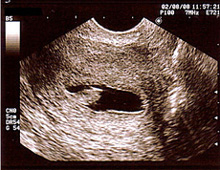

超音波検査(エコー)

卵胞の測定(卵子を含んでいる液体の袋)

卵胞は約20ミリになると排卵します。正確な排卵日と排卵状態を診断します。

- 子宮内膜の厚さの測定

通常、排卵直前の内膜は三層構造で8ミリ以上が望ましい。 - 子宮筋腫、子宮内膜症、卵巣嚢腫などの診断。